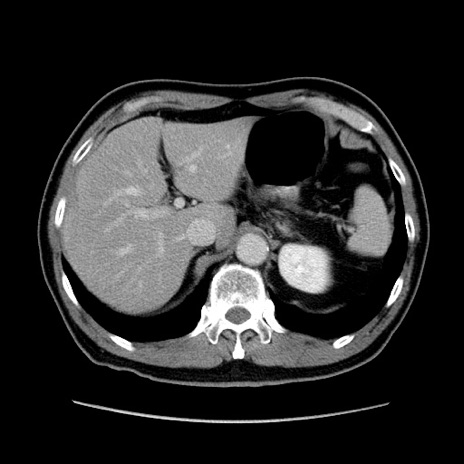

症例34(横断像)

【症例】60歳代 男性

【主訴】右鼠径部膨隆

【現病歴】1年程前より右鼠径部膨隆あり。自己にて還納可能だったため放置していた。3時間前より右鼠径部の脱出を認め、還納困難となり受診。

【身体所見】右鼠径部に小児頭大の膨隆あり。弾性硬であり、用手還納は困難。左鼠径部にも膨隆を認める。脱出はなし。